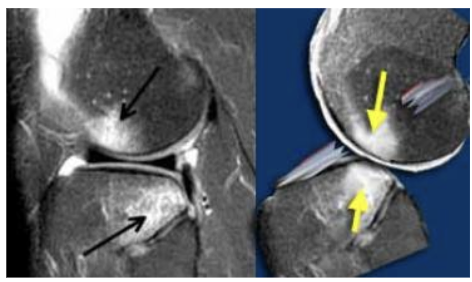

concurrent bone bruising most common where

A

over lateral femoral condyle

bone bruises heal slow

The inner bone/trabecular bone can fracture and take 2-3 months – up to one year to heal

A kissing contusion (seen on MRI) is a strong indicator of an ACL tear; however, may be meniscus, or both. Can occur in isolation.